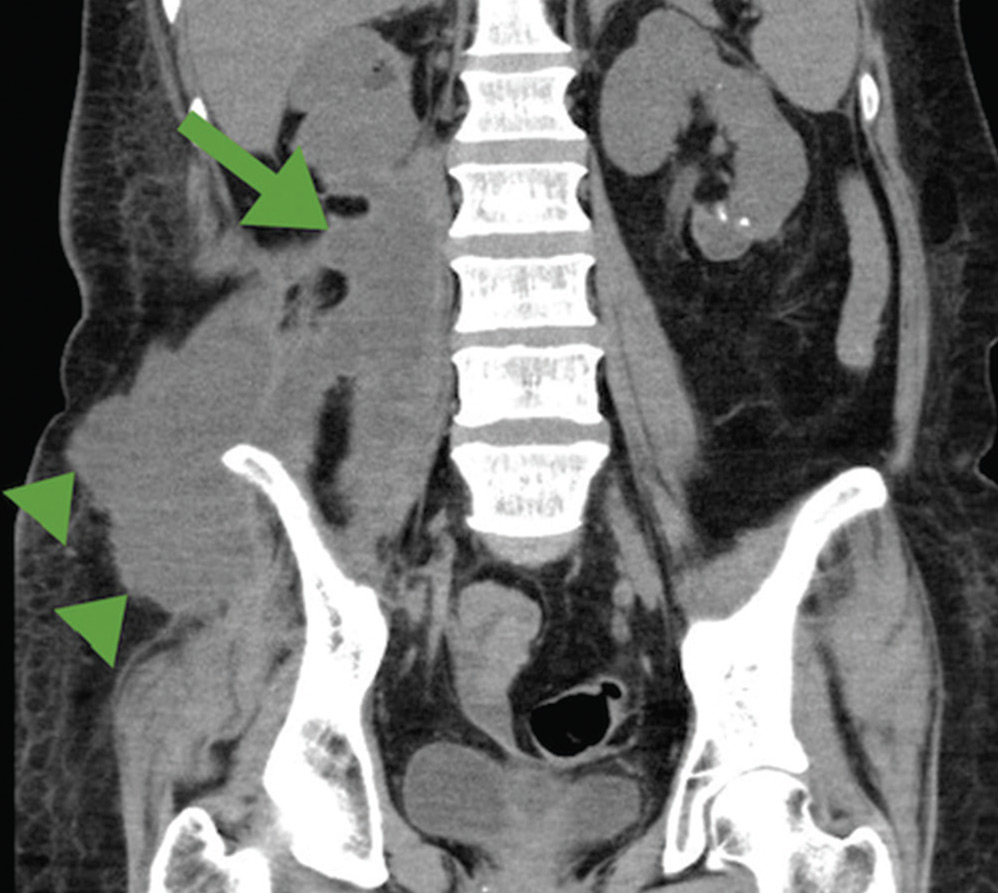

- МСКТ (компьютерная томография). Данная процедура помогает судить о распространенности воспалительного процесса. А также о его взаимоотношениях с близлежащими тканями и внутренними органами. Однако этот метод имеет и недостаток — дополнительная лучевая нагрузка на обследуемого.

- УЗИ (ультразвуковое исследование органов брюшной полости). С помощью данной процедуры тоже возможно выявить гнойно-воспалительные процессы, затронувшие подвздошно-поясничную мышцу, а также их объем. Но в сравнении с вышеобозначенными это менее точный метод. Тем не менее звуковое обследование практически всегда позволяет найти источник распространения инфекции, масштабность проистекающего воспалительного процесса, а также оценить, насколько он затронул соседние органы и ткани.